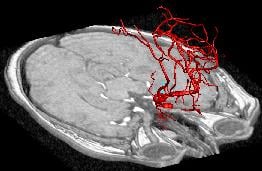

Mission: NECSTR is a neuroradiology facility that offers the latest technology in image guided intervention to support University investigators in developing minimally invasive treatments.

NECStR has been fully operational since May 3 2007 with a special focus is on image guided interventions for minimally invasive treatment of vascular disease. The center’s expertise and resources enable animal modeling of vascular pathologies, 3D x-ray imaging, post acquisition image processing, rapid prototyping from medical imaging and image guided minimally invasive surgery. Although the center’s focus lies in cardiovascular imaging and intervention, previous work has included selective vascular drug delivery for cancer treatment and orthopedic device implantation.